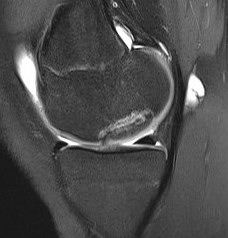

MFC unstable OCD

LFC unstable OCD